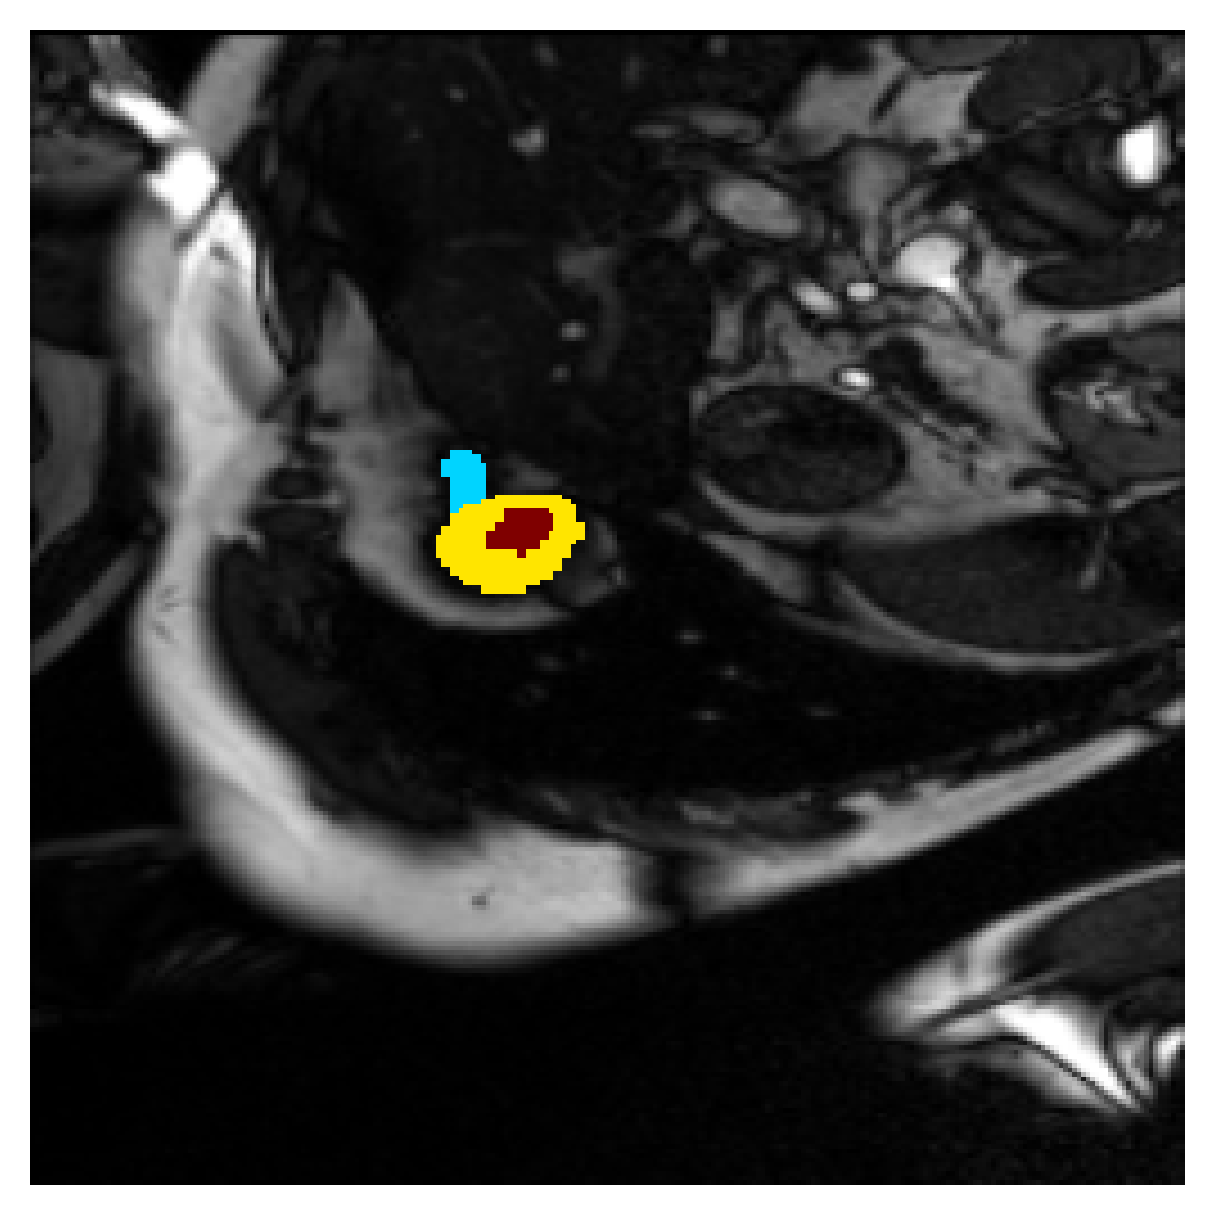

We normalize the volumes and resize the slices to pixels. As the official dataset comes with full annotations, we create a synthetic point ground truth. This is done by first randomly choosing the centers of the point annotations within the class masks, followed by filling an ellipse with axes lengths of and (in pixels) around each center. The intersections of these elliptic discs with the underlying full annotations are then used as our point ground truth. See Figure 2 for an example of the created weak annotation mask. The point annotations are created for every slice, one for each foreground object present in the slice.

Qualitative comparison

|

|

|||

|

|

|

|

|

|

|

|

|

|

|

|

| (a) Ground truth | (b) , full | (c) , weak | (d) |

| (full) | supervision | supervision | |

|

|

|

|

|

|

|

|

|

|

|

|

| (e) | (f) | (g) | (h) CRF-loss |

In Figure 6 we provide qualitative results on a number of randomly chosen test set slices. Upon visual inspection, we can observe that training with the intensity-aware distances (particularly with and ) follows the image gradients better and is better at recovering the underlying shape than the Euclidean version. The CRF-loss seems to recover the shape of the myocardium and left ventricle to some extent, but fails entirely on the right ventricle.